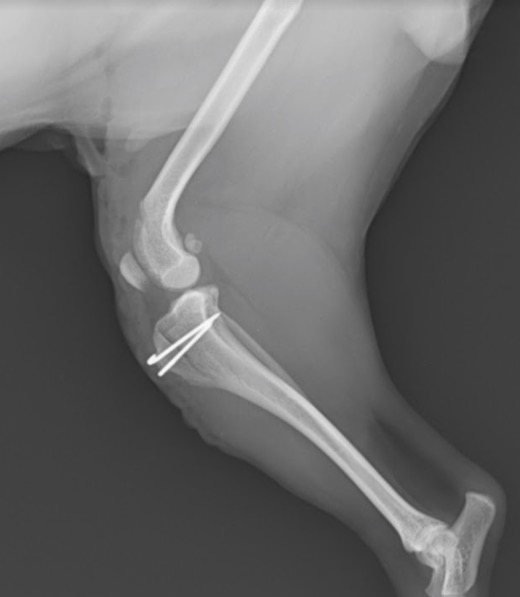

脛骨粗面転位手術 : 脛骨粗面を移動しピンで固定しています。